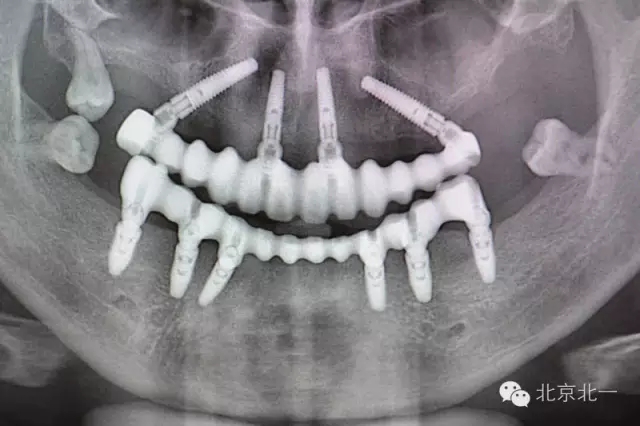

圖五:術(shù)后全景片

圖八:戴牙后復(fù)查全景片